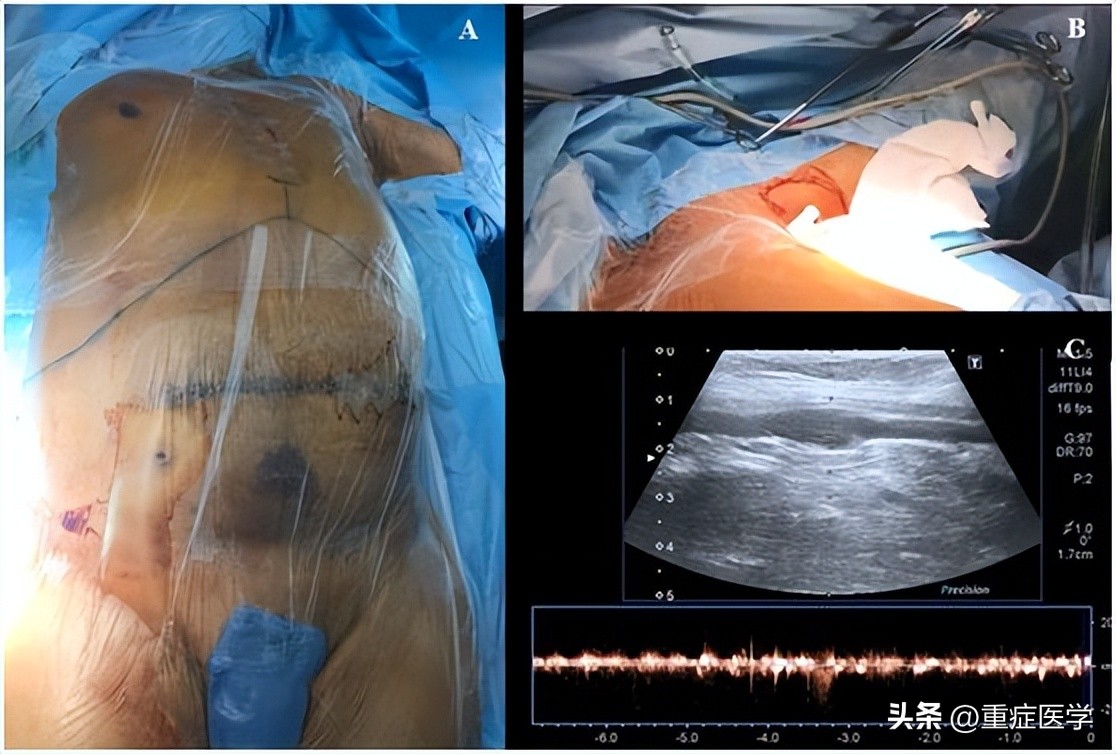

操作前,将患者置于平躺仰卧位,头部自然居中位,左上肢掌心向上外展90度(图1,A)。超声探头上涂上耦合剂,用无菌保护套包裹超声探头及导线。

从上臂近端至腋窝处超声预扫描,同时探查腋动脉和腋静脉的长轴平面(图1,BC),注意用最小的压力来控制超声探头,避免把血管压瘪。然后用多普勒和/或彩色血流来评估静脉及动脉的通畅性。

图1,A肝移植术患者体位,B-C腋静脉超声预扫描。